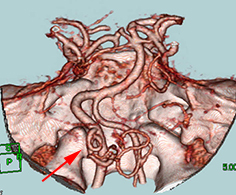

左後下小脳動脈(矢印)は術後に本来の位置から移動している。

舌咽神経への血管圧迫が解除されたため、術後に患者様は舌咽神経痛が消失した。